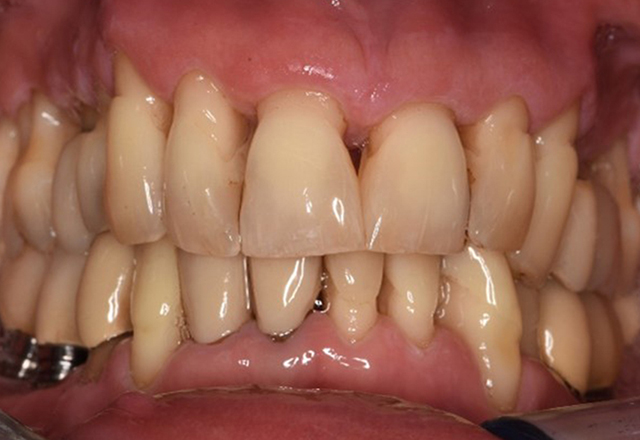

The transplant patient with gingival overgrowths

A 71-year old patient presents with having previously undergone a kidney transplant and with a history of hypertonia (high blood pressure). Due to his medical history, long-term medication with cyclosporine is required to suppress the immune system, as well as amlodipine to lower blood pressure. The patient also reports sensitive and bleeding gums. From an oral health perspective, the patient has undergone dental restoration and has eight missing teeth, pronounced gingival growth, and grade B, stage II periodontitis with active pockets and initial root caries on tooth 22. The caries risk assessment determines a moderate risk of caries (API 60). The following treatment recommendations can be determined for the prophylaxis session. more

The healthy patient with early periodontal disease

The 68-year-old patient has no general health conditions and is not taking any medication that may be relevant to her oral health, and her lifestyle does not pose any particular risk. The patient has two dental implants (3rd quadrant, for five years) and a previous case of periodontal disease (stage IV, grade B periodontitis) with tooth loss. Currently the periodontal conditions are stable. However, periodontitis significantly increases the biological complications of implantations and there is a risk of implant loss (21). Four recommendations can be determined for the prophylaxis session. more